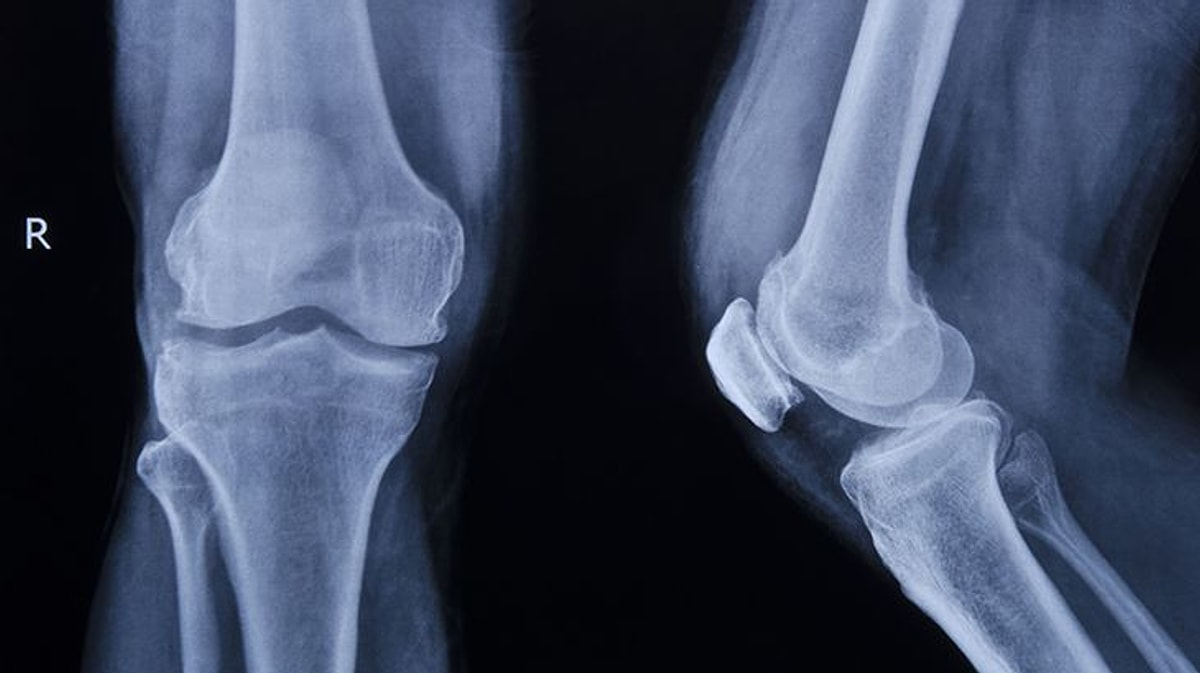

Хай, пикабу. Помогите пожалуйста. Задумал сделать художественный проект про атроз суставов, а для этого нужны ренгеновские снимки. Не могу еще найти. Есть своих два, а нужно больше. Может кто-то может поделиться ренгеновскими снимками своими данного заболевания. Нужно их использовать в проекте.